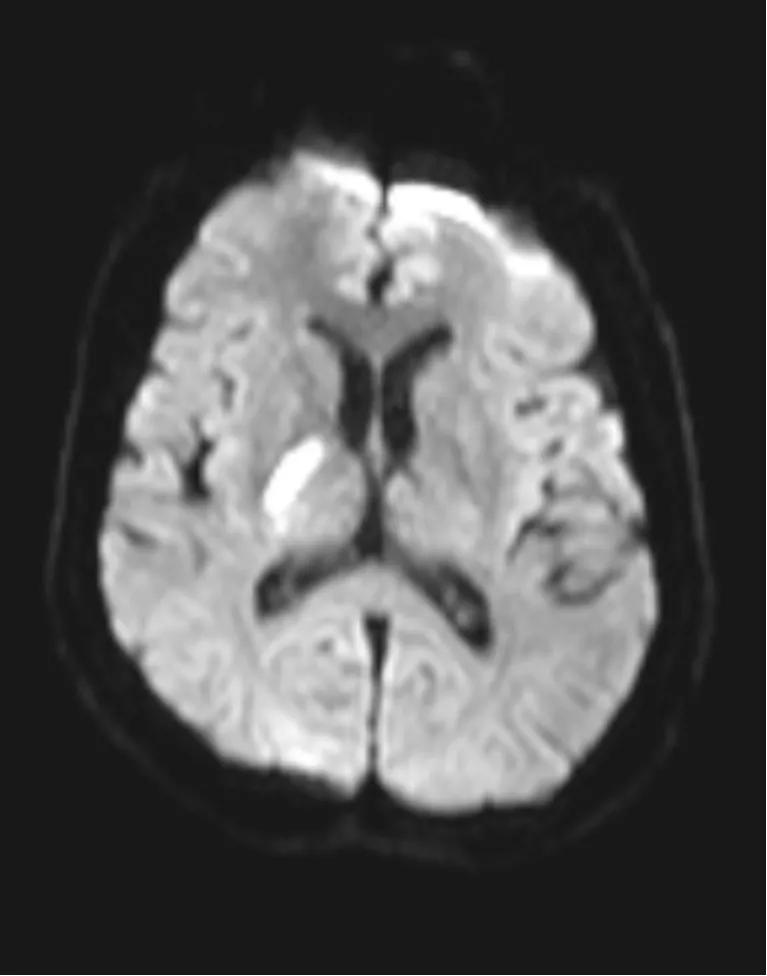

病例一

男性49岁患者,主诉:发作性左侧肢体无力7小时,持续不缓解40分钟。医生根据患者情况进行溶栓评估,并给予阿替普酶静脉溶栓。溶栓前左侧肢体不能活动,呈完全瘫痪状态,溶栓前NIHSS(代表神经缺损程度,评分越高缺损越严重)评分10分,溶栓结束评分降至3分,左侧肢体肌力基本恢复正常,该患者静脉溶栓无出血、过敏等并发症,出院时肢体活动正常。

脑梗死责任病灶